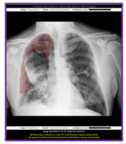

On-device, CCS2.1 output from GE HealthCare's AMX Navigate mobile X-ray system showing PTX overlay and confidence level. (Photo: GE HealthCare)

With this latest update, Critical Care Suite 2.1 provides immediate on-device detection and triage notifications for the presence or absence of pneumothorax (PTX). When a PTX is detected, an overlay is displayed in the area where the PTX was located both on-device as well as in PACS to assist with PTX localization, as well as improve speed and accuracy of PTX diagnosis. By hosting Critical Care Suite on-device, critical insights are available at the point of care and across the entire clinical care team.